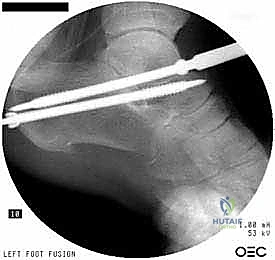

5. التثبيت الميكانيكي (Fixation)

بعد وضع العظام في الزاوية التشريحية الصحيحة تماماً، يتم تثبيتها بقوة لضمان عدم حركتها أثناء فترة الشفاء. يستخدم الدكتور هطيف مسامير ضغط كبيرة من التيتانيوم (Cannulated Screws). يتم إدخال هذه المسامير (عادة مسمارين) عبر عظم الكعب صعوداً إلى عظم الكاحل، وتعمل على ضغط العظمتين معاً بقوة هائلة، مما يوفر بيئة مثالية للاندماج.

بعد التأكد من وضع المسامير بشكل مثالي باستخدام جهاز الأشعة التداخلية (C-arm) داخل غرفة العمليات، يتم إغلاق الشق الجراحي بغرز تجميلية، وتوضع القدم في جبيرة خلفية مبطنة جيداً للحماية.